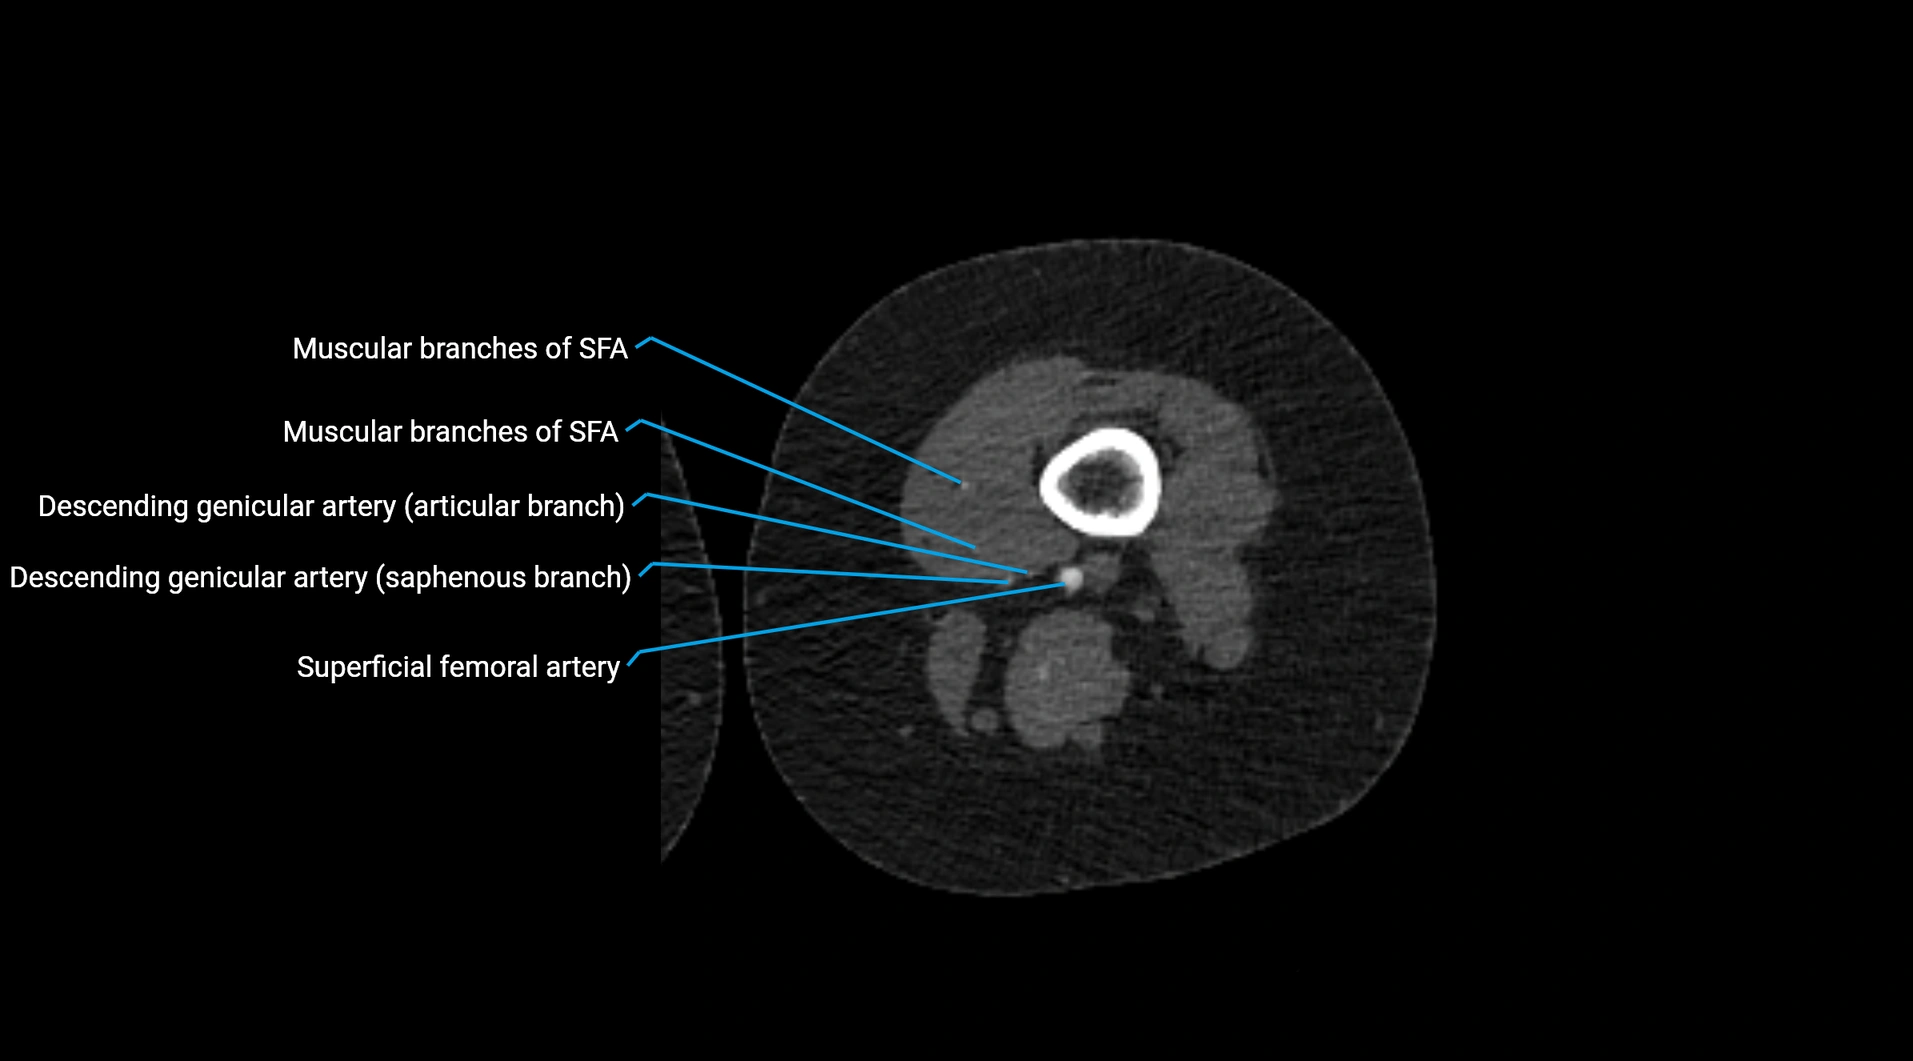

CT Appearance

Non-contrast CT:

• Appears as a tubular soft tissue structure anterior to vertebral bodies

• Calcified atherosclerotic plaques appear as hyperdense foci along the wall

• Useful for screening abdominal aortic aneurysm (AAA) size and mural calcification

Contrast-enhanced CT (CTA):

• Gold standard for abdominal aortic imaging

• Provides excellent detail of lumen, wall, aneurysm, thrombus, and branch vessels

• Multiplanar and 3D reconstructions help in aneurysm measurement, stent graft planning, and dissection evaluation

• Detects acute rupture, traumatic injury, or occlusion with high sensitivity